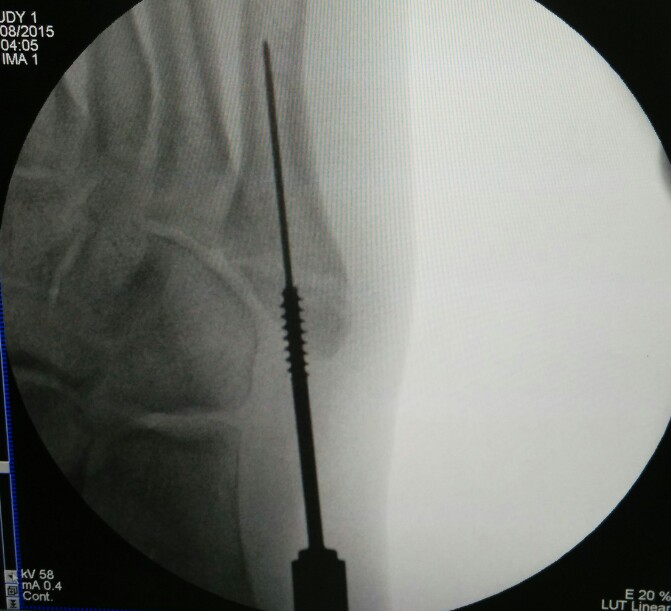

Percutaneous cannulated screw fixation of this displaced avulsion fracture of the 5th metatarsal base was performed.

This procedure is done via a small incision and guided by x-rays fluroscopy.

This is the final result:

The patient was able to bear weight on the right foot and walk by the 2nd week after surgery.